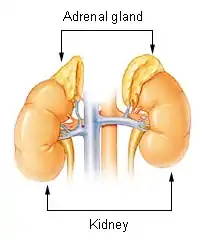

The ACTH test (also called the cosyntropin, tetracosactide, or Synacthen test) is a medical test usually requested and interpreted by endocrinologists to assess the functioning of the adrenal glands' stress response by measuring the adrenal response to adrenocorticotropic hormone (ACTH; corticotropin) or another corticotropic agent such as tetracosactide (cosyntropin, tetracosactrin; Synacthen) or alsactide (Synchrodyn).[1][2] ACTH is a hormone produced in the anterior pituitary gland that stimulates the adrenal glands to release cortisol, dehydroepiandrosterone (DHEA), dehydroepiandrosterone sulfate (DHEA-S), and aldosterone.[3]

During the test, a small amount of synthetic ACTH is injected, and the amount of cortisol (and sometimes aldosterone) that the adrenals produce in response is measured.[4] This test may cause mild side effects in some individuals.[5][6]

This test is used to diagnose or exclude primary and secondary adrenal insufficiency, Addison's disease, and related conditions.[2] In addition to quantifying adrenal insufficiency, the test can distinguish whether the cause is adrenal (low cortisol and aldosterone production) or pituitary (low ACTH production).[1] The Insulin tolerance test is recognized as the gold standard assay of adrenal insufficiency, but due to the cumbersome requirement for a two-hour test and the risks of seizures or myocardial infarction, the ACTH stimulation test is commonly used as an easier, safer, though not as accurate, alternative.[7] The test is extremely sensitive (97% at 95% specificity) to primary adrenal insufficiency, but less so to secondary adrenal insufficiency (57-61% at 95% specificity); while secondary adrenal insufficiency may thus be dismissed by some interpreters on the basis of the test, additional testing may be called for if the probability of secondary adrenal insufficiency is particularly high.[1]

Aldosterone stimulation

The ACTH stimulation test is occasionally used to test adrenal production of aldosterone at the same time as cortisol to also help in determining if primary (hyperreninemic) or secondary (hyporeninemic) hypoaldosteronism is present.[4] Human ACTH has a slight stimulatory effect on aldosterone,[19] but the amount of synthetic ACTH given in the stimulation is equivalent to more than a whole days production of natural ACTH, so the aldosterone response can be easily measured in blood serum.[20] Same as cortisol, aldosterone should double from a respectable base value (around 20 ng/dl, must fast salt 24 hours and sit upright for blood draw) in a healthy individual.